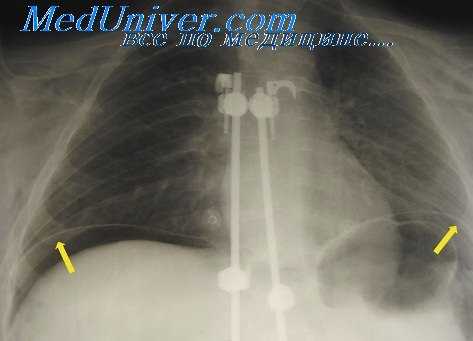

- Лучевая диагностика. Рентгенография и КТ грудной клетки являются наиболее информативными методами исследования диафрагмы. На рентгенограмме визуализируется высокое расположение одного из куполов (уровень II–V ребра). При рентгеноскопии обнаруживается парадоксальное движение диафрагмального свода. Использование контраста позволяет выявить перегибы пищевода, желудка, смещение органов пищеварения кверху. КТ наиболее точно определяет степень релаксации, помогает распознать вторичную патологию внутренних органов.